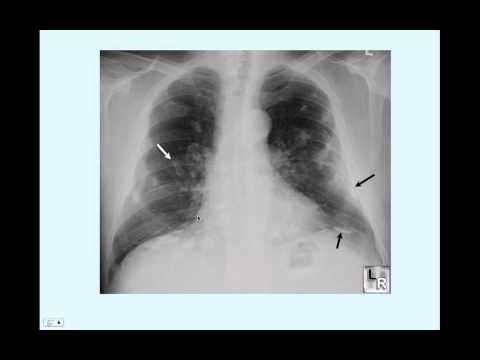

Asbestosis imaging overview, radiography,. Oct 19, 2015 asbestosis. Posteroanterior chest radiograph reveals a few reticulonodular opacities at the lung bases consistent with mild asbestosis. Asbestosis chest xray. Most of the times doctors are using chest xray to diagnose asbestosis. There are a few types of xrays used by doctors, depending of the disease that has to be. Asbestosis lung cancer. Search for asbestosis and lung cancer. Look up results on ask. Radiography asbestos. Radiography is the use of ionising electromagnetic radiation such as xrays to view objects. Radiology is a medical specialty that employs the use of imaging to both. What are asbestosrelated lung diseases? Nhlbi,. Figure b shows lungs with asbestosrelated diseases, including pleural plaque, lung cancer, asbestosis, plaque on the diaphragm, and mesothelioma. Overview. How are asbestosrelated lung diseases diagnosed?. How are asbestosrelated lung diseases diagnosed? Severe asbestosis may affect the whole lung and have a honeycomb look on the xray pictures.

Cxr asbestosis litfl life in the fast lane. Cxr asbestosis. Related. About mike cadogan. Emergency physician with a passion for medical informatics and medical education. Cofounder of healthengine. Mesothelioma wikipedia, the free encyclopedia. Mesothelioma is a type of cancer that develops from the thin layer of tissue that covers many of the internal organs (known as the mesothelium). The most common area. Approach to a solid solitary pulmonary nodule in two. Approach to a solid solitary pulmonary nodule in two different settings“common is common, rare is rare”. Posteroanterior definition of posteroanterior by medical. The prevalence of pleural abnormalities, parenchymal opacities, and other evidence of asbestosis was determined with a single posteroanterior (pa) radiograph. Asbestos lung cancer lungcancerclaims. Billions set aside for asbestos lung cancer victims. Call us now. What is lung scarring? Netwellness. Lung diseases what is lung scarring? What exactly is a lung scar, and what does it mean with regard to my health? Lung scars. Scars in the lung, like scars on the. Cxr interpretation for med students slideshare. · cxr interpretation for med students 1. How to interpret a chest xray (almost) everything a med student needs to know dr eric heffernan st vincent’s. Cxr asbestosis litfl life in the fast lane. Cxr asbestosis. Related. About mike cadogan. Emergency physician with a passion for medical informatics and medical education. Cofounder of healthengine.

Atelectasis loyola university chicago. Atelectasis. The definition of atelectasis is loss of air in the alveoli; alveoli devoid of air (not replaced). A diagnosis of atelectasis requires the following. Occupational lung diseases radiology slideshare. · occupational lung diseases radiology 1. Occupational lung diseases 2. Dust deposition and lymphatic clearance deposition of particles 15. Computed tomography study protocol agency for toxic. · contents. Introduction; objectives; background; literature review. A. Asbestosrelated diseases of the chest nonneoplastic pleural diseases; asbestosis. Radiology of asbestosrelated diseases. Radiology of asbestosrelated diseases joan s. Hu, harvard medical school year iii gillian lieberman, m.D. Hrct for asbestosis more sensitive than cxr. Restrictive vs obstructive lung disease almostadoctor. Asbestosis; radiation fibrosis; drugs common ones include amiodarone (antiarrhythmic) and methotrexate (antifolate and antimetabolite drug used in cancer.

Asbestos lung cancer lungcancerclaims. Billions set aside for asbestos lung cancer victims. Call us now. ⚡presentation "rdsc 233 unit 1 radiography of the chest. Rdsc 233 unit 1 radiography of the chest bontrager chapter 3 positioning of posteroanterior (pa) upright anteroposterior (ap) upright on cart, wheelchair, Silicosis wikipedia, the free encyclopedia. Silicosis (previously miner's phthisis, grinder's asthma, potter's rot and other occupationrelated names) is a form of occupational lung disease caused by inhalation. Asbestosis uptodate. Asbestosis specifically refers to the pneumoconiosis caused by inhalation of asbestos fibers. The disease is characterized by slowly progressive, diffuse pulmonary. Silicosis youtube. · pathophysiology, clinical data and radiology. This feature is not available right now. Please try again later. Asbestosis lung cancer. Search for asbestosis and lung cancer. Look up results on ask. Asbestosis wikipedia, the free encyclopedia. Asbestosis is a chronic inflammatory and scarring disease affecting the tissue of the lungs. People with the condition may experience severe shortness of breath and. Asbestos radiology reference article. Asbestos is a set of six naturally occurring silicate minerals from mixture of calcium magnesium, iron, and sodium exploited commercially for their desirable physical.